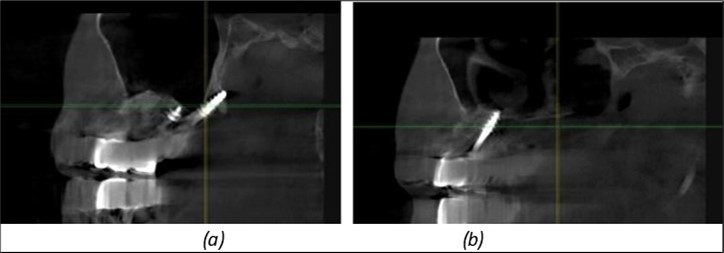

Figure 9.Implants in the pterygoid plateau area: (a) TPG implant fixed in the maxillary-sphenoid junction area, quadrant 1; (b) TPG implant fixed in the maxillary-sphenoid junction area, quadrant 2.

Figure 10.Implants in the palatal sinus cortical area to avoid bone grafting: (a) BCS implant partially fixed in the graft material mass, partially in the palatal cortex; (b) Implant fixed in the palatal cortex at the junction with the nasal cortex, behind the graft material mass.